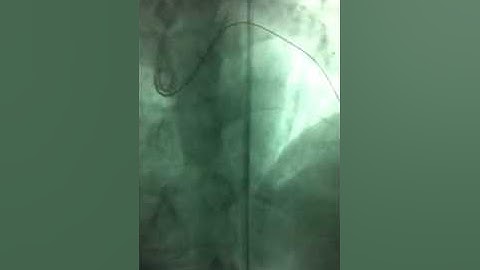

Subcutaneous Fat Embolization for Management of Coronary Perforation During Retrograde CTO-PCI